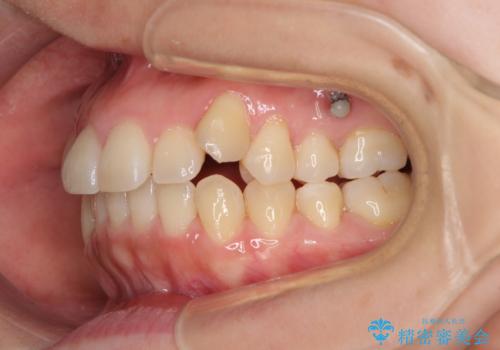

- 八重歯と前歯のデコボコを気にして来院された患者様です。

八重歯の他に、上顎歯列を狭窄しているという問題点がありました。

また、八重歯により上顎奥歯が前方に位置しており、咬み合わせの改善も必要な状況でした。

八重歯の動きが鈍く、治療期間は長期化しました。

癒着の疑いもありましたが、アンカースクリューを多用し、何とか改善することができました。